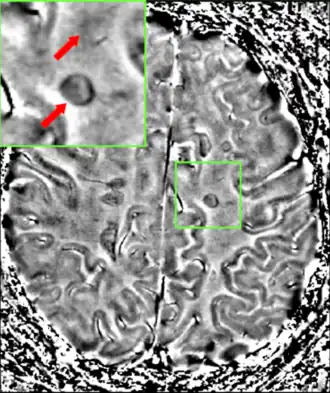

MRI

Magnetic resonance imaging (MRI) of the brain and spine may show areas of demyelination (lesions or plaques). Gadolinium can be administered intravenously as a contrast agent to highlight active plaques, and by elimination, demonstrate the existence of historical lesions not associated with symptoms at the moment of the evaluation.[94][95]

Central vein signs (CVSs) have been proposed as a good indicator of MS in comparison with other conditions causing white lesions.[96][97][98][99] One small study found fewer CVSs in older and hypertensive people.[100] Further research on CVS as a biomarker for MS is ongoing.[101]